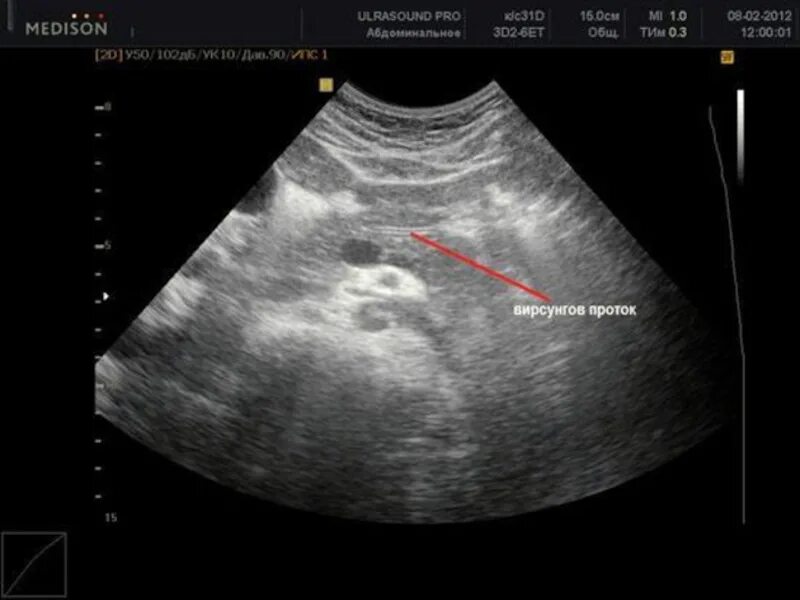

Расширен проток